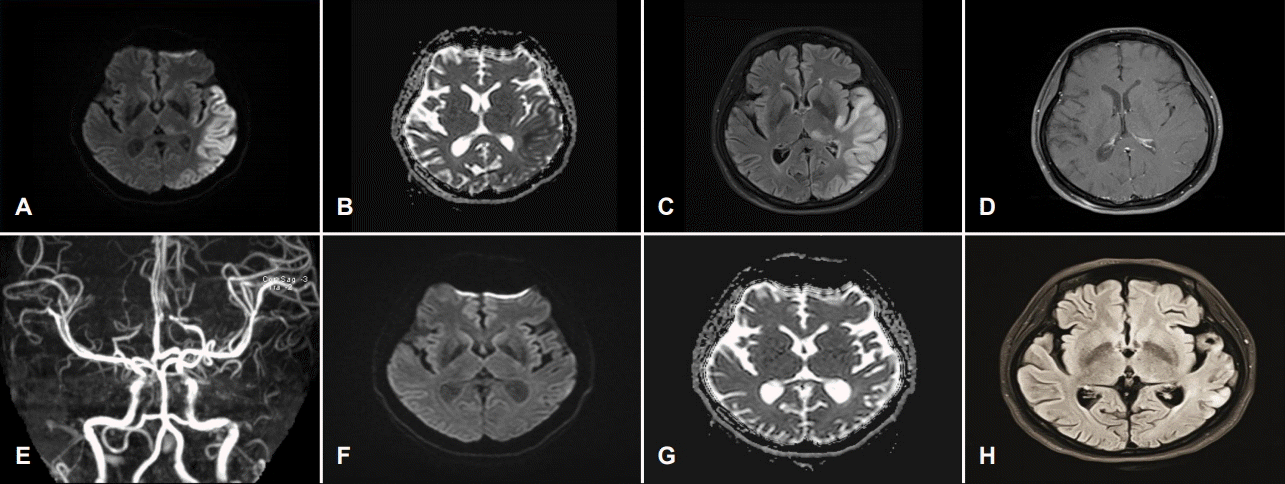

Figure 1.

(A-D) Magnetic resonance image performed on admission day and (E-G) follow up after 4 months. (A) Diffusion weighted image (DWI) and (B) apparent diffusion coefficient (ADC) images show diffusion restriction (DWI high signal intensity and decreased ADC value) in the left temporal, occipital lobes and thalamus. (C) Fluid attenuation inversion recovery (FLAIR) shows high signal intensity and edematous change in the corresponding area. (D) Gadolinum-enhanced T1 weighted image does not show enhancement on the lesion. (E) Time of flight-magnetic resonance angiography does not show definite stenosis or occlusion in the left middle cerebral arterial territory and appear hypervascularized in the same area. (F) Follow up DWI image and (G) ADC map after 4 months shows disappeared diffusion restriction in the left temporal, occipital cortices and thalamus. (H) Follow up FLAIR image shows disappeared high signal intensity except in the left temporal cortex.